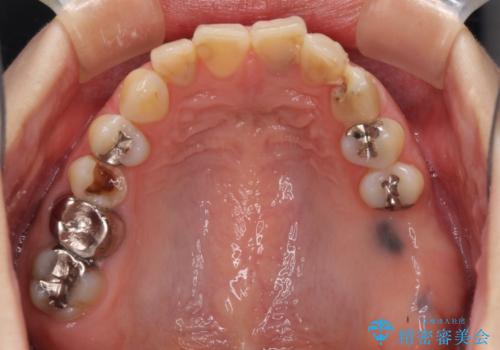

- 長年むし歯を放置してしまっているとのことで来院された患者様です。

神経が除去されている歯、根管治療の必要な歯、むし歯の非常に大きな歯に対してオールセラミッククラウンにて補綴治療を行うこととしました。

左上の欠損部はインプラントを埋入した上で補綴することとしました。